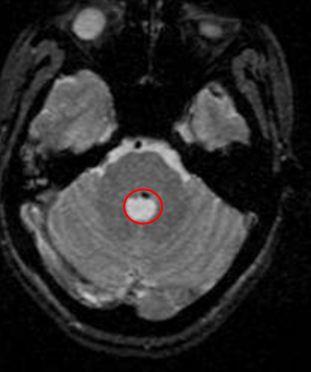

Tại khoa thần kinh bệnh viện Bạch Mai bệnh nhân nhanh chóng được chẩn đoán xác định bệnh; bệnh nhân được chụp phim cộng hưởng từ (MRI) sọ não cho thấy có hình ảnh khối u máu thể hang (cavernoma) tại vùng cầu não (thuộc thân não) bên trái, kích thước 14mm. Sau đó bệnh nhân được chuyển đến Trung tâm Y học hạt nhân và Ung bướu - Bệnh viện Bạch Mai.

Vị trí khối tổn thương u máu thể hang cavernoma) vùng thân não : hình màu đen bên trong hình đỏ.